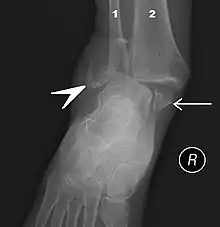

.jpg)

Traumatic injury

Of all major joints, the ankle is the most commonly injured. If the outside surface of the foot is twisted under the leg during weight bearing, the lateral ligament, especially the anterior talofibular portion, is subject to tearing (a sprain) as it is weaker than the medial ligament and it resists inward rotation of the talocrural joint.[8]: 825

Fractures

An ankle fracture is a break of one or more of the bones that make up the ankle joint.[20] Symptoms may include pain, swelling, bruising, and an inability to walk on the injured leg.[20] Complications may include an associated high ankle sprain, compartment syndrome, stiffness, malunion, and post-traumatic arthritis.[20][21]

Ankle fractures may result from excessive stress on the joint such as from rolling an ankle or from blunt trauma.[20][21] Types of ankle fractures include lateral malleolus, medial malleolus, posterior malleolus, bimalleolar, and trimalleolar fractures.[20] The Ottawa ankle rule can help determine the need for X-rays.[21] Special X-ray views called stress views help determine whether an ankle fracture is unstable.

Treatment depends on the fracture type. Ankle stability largely dictates non-operative vs. operative treatment. Non-operative treatment includes splinting or casting while operative treatment includes fixing the fracture with metal implants through an open reduction internal fixation (ORIF).[20] Significant recovery generally occurs within four months while completely recovery usually takes up to one year.[20]

Ankle fractures are common, occurring in over 1.8 per 1000 adults and 1 per 1000 children per year.[21][22] In North America this figure increases to more than 14 in ever 10,000 patients admitted to the Emergency Room.[23] They occur most commonly in young males and older females.[21]Imaging

The initial evaluation of suspected ankle pathology is usually by projectional radiography ("X-ray").

For ligamentous injury, there are three main landmarks on X-rays: The first is the tibiofibular clear space, the horizontal distance from the lateral border of the posterior tibial malleolus to the medial border of the fibula, with greater than 5 mm being abnormal. The second is tibiofibular overlap, the horizontal distance between the medial border of the fibula and the lateral border of the anterior tibial prominence, with less than 10 mm being abnormal. The final measurement is the medial clear space, the distance between the lateral aspect of the medial malleolus and the medial border of the talus at the level of the talar dome, with a measurement greater than 4 mm being abnormal. Loss of any of these normal anatomic spaces can indirectly reflect ligamentous injury or occult fracture, and can be followed by MRI or CT.[26]